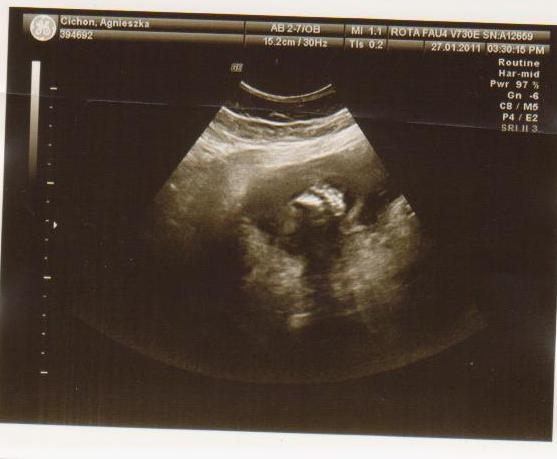

cześć dziewczyny to i ja chciałabym do Was dołączyć, właśnie znalazłam to forum. Mieszkam w Irlandii od 4 lat i mam synka 21 miesięcy, a teraz jestem w 28 tc bliźniaczej :-) dwie dziewczynki dwujajowe :-) też mnie trochę przeraża poród bliźniaków ale trzeba jakoś urodzić ;-) Pierwszy poród miałam jak marzenie szybko, sprawnie i nawet bez znieczulenia, mam nadzieję że i tym razem bęzie podobnie.

Hej podwojne mamunie:-)Ja juz rozpakowana dawno mamusia dubeltowka.Gratuluje wam serdecznie i witam w gronie tych wybranych hihiNiczego sie nie bojcie.Ciaxa blizniacza jest pod specjalna opieka.Czekaja was czeste wizyty w szpitalu i czeste ogladanie maluszkow na usg :-)